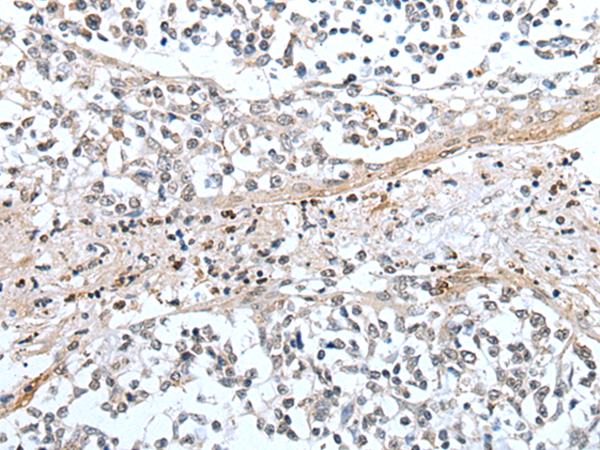

IHC positive control: |

Human prostate cancer and human tonsil |